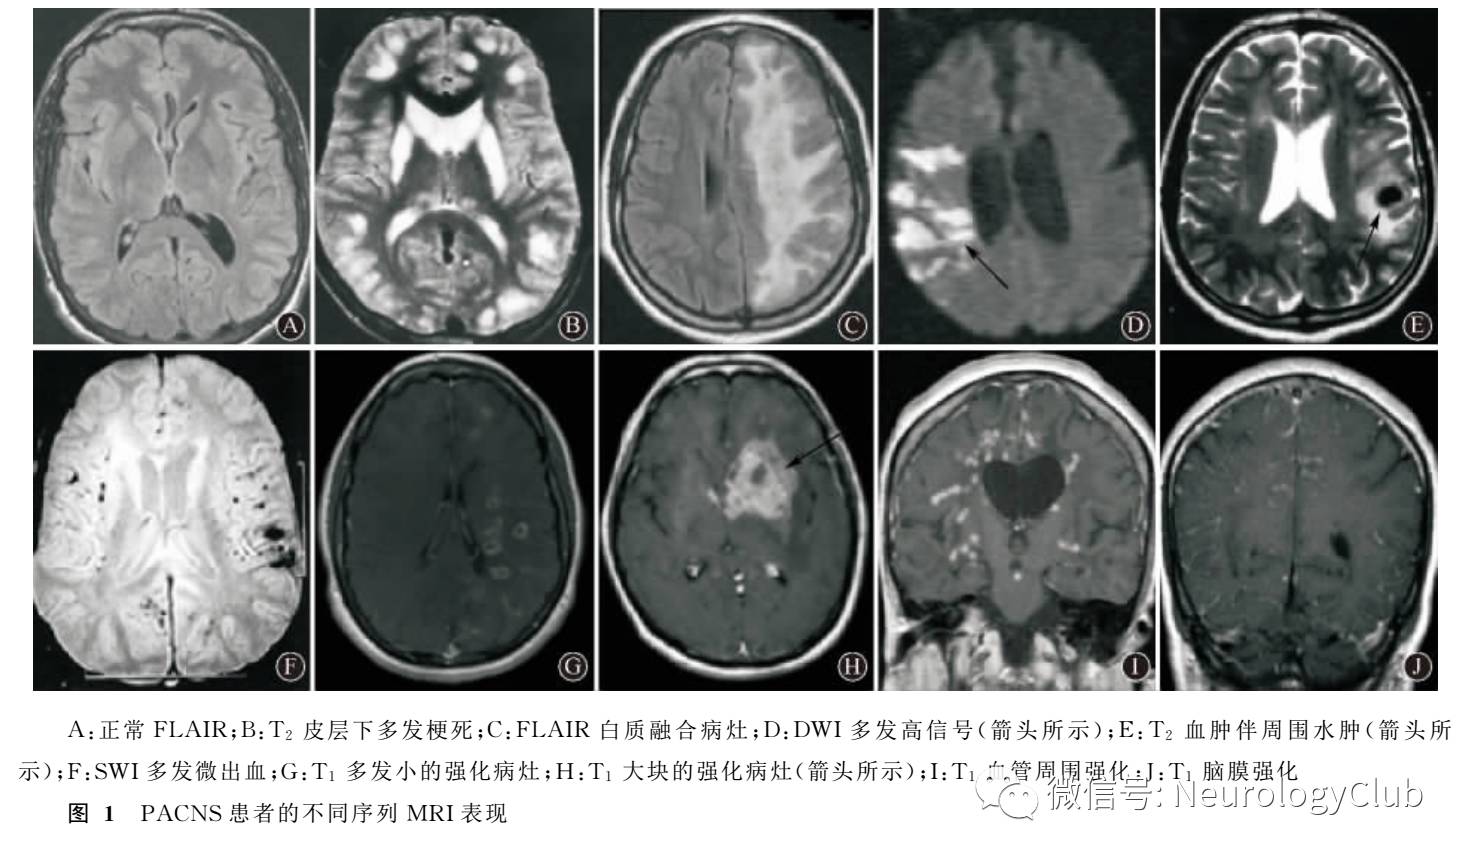

3.2.2 MRIMRI是对PACNS最敏感的影像学检查方法,PACNS患者通过MRI检查约90%-100%可有阳性发现。应用MRI不同的序列成像方法更容易发现PACNS的异常表现,常见的颅脑MRI异常表现有以下10种,具体见图1。

(1)正常这种情况见于少数PACNS早期,此时可通过磁灌注成像来提高诊断敏感性

(2)同时累及皮层和皮层下的多发梗死:此种情况在PACNS中较常见,可呈中血管或其分支供血区梗死,也可表现为小动脉型梗死,常见部位依次为皮层下白质、深部灰质、深部白质、皮层,呈T2、FLAIR高信号

(3)进行性融合的白质病灶,此表现易被误诊为脱髓鞘疾病

(4)DWI多发高信号,可见于PACNS急性期

(5)脑实质内大小血肿

(6)脑实质多发微出血梯度回旋MRI SWI可表现为无症状的多发斑点状微出血灶,结合其他序列的多发缺血证据,更利于诊断PACNS

(7)脑实质多发小的强化病灶

(8)单发或多发大块强化病灶,可伴水肿、小血管强化,易被误诊为肿瘤

(9)血管周围间隙扩大伴强化

(10)软脑膜的强化病灶,此表现可见于约9%的PACNS